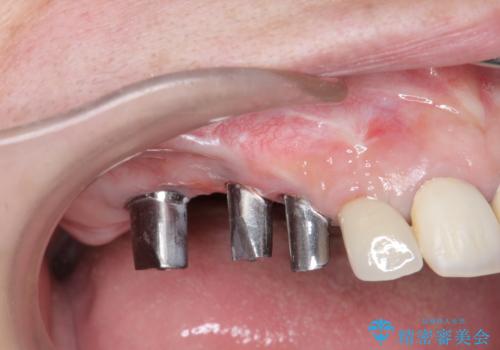

既に埋入されているインプラントは位置が悪いのでそのまま骨内に留置することとし、新たに咬合機能を回復すべく3本のインプラントを埋入すると同時に吸収した骨幅を増やし、安定してインプラントで噛める環境整備を目指します。

- 120万円(インプラント×3 チタンカスタムアバットメント×3 メタルボンドクラウン×3 骨造成 歯肉移植)費用は治療当時の料金となります

インプラントが長持ちするために、インプラント周囲の十分な骨量・角化歯肉の存在・安定した咬合を一つづつ整備する治療を行いました。